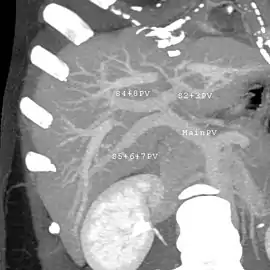

Axial CT image showing anomalous hepatic veins coursing on the liver's subcapsular anterior surface[66]

Axial CT image showing anomalous hepatic veins coursing on the liver's subcapsular anterior surface[66] Maximum intensity projection (MIP) CT image as viewed anteriorly showing the anomalous hepatic veins coursing on the anterior surface of the liver

Maximum intensity projection (MIP) CT image as viewed anteriorly showing the anomalous hepatic veins coursing on the anterior surface of the liver Lateral MIP view in the same patient as previous image

Lateral MIP view in the same patient as previous image A CT scan in which the liver and portal vein are shown

A CT scan in which the liver and portal vein are shown